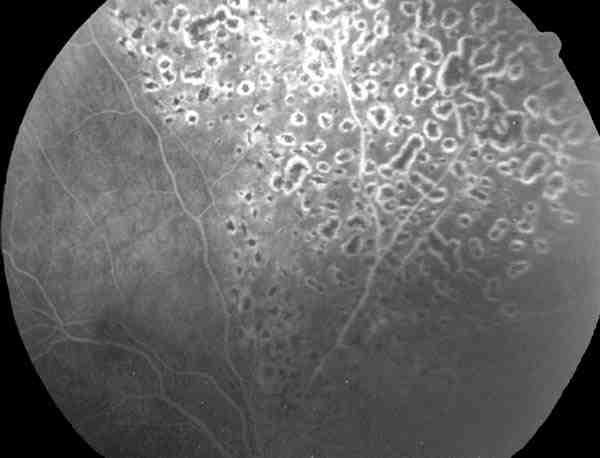

Figura 10

AFG DEL MISMO CASO QUE FIGURA 7, REGRESIÓN DE NEOVASCULARIZACIÓN TRAS FOTOCOAGULACIÓN.